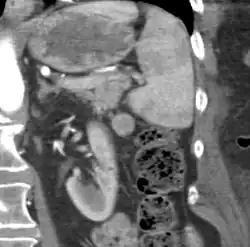

| CT scan of an accessory spleen (circular object in center of image) between the spleen and left kidney. | |

An accessory spleen is a small nodule of splenic tissue found apart from the main body of the spleen. Accessory spleens are found in approximately 10 percent of the population[1] and are typically around 1 centimeter in diameter. They may resemble a lymph node or a small spleen. They form either by the result of developmental anomalies or trauma.[2] They are medically significant in that they may result in interpretation errors in diagnostic imaging[2] or continued symptoms after therapeutic splenectomy.[1] Polysplenia is the presence of multiple accessory spleens rather than one normal spleen.